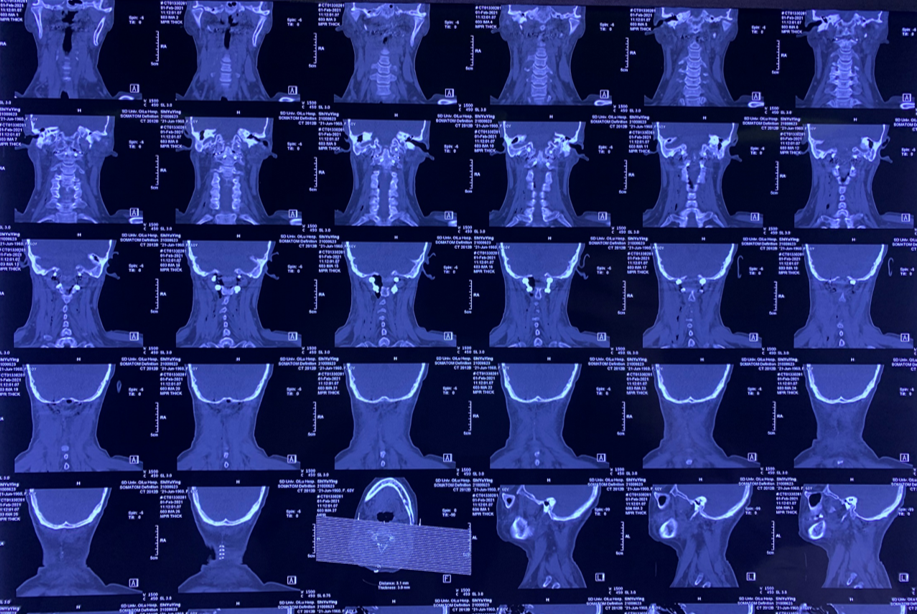

颈椎CT:

颈椎退行性变,C2/3、C3/4、C4/5、C5/6、C6/7椎间盘突出并C4/5水平椎管狭窄;符合颅底凹陷症合并寰枕融合,寰枢关节脱位CT表现。

颅底凹陷症、寰枕融合;寰枢关节脱位并延髓脊髓变性或损伤;颈椎退行性变;C2/3、C3/4、C4/5、C5/6、C6/7椎间盘突出并C4/5水平椎管狭窄。

患者术前部分影像学资料

影像学资料显示寰枢椎脱位,脊髓受压明显

术后复查枕颈X线、CT、MR结果

影像学检查显示齿状突复位良好,脊髓减压充分